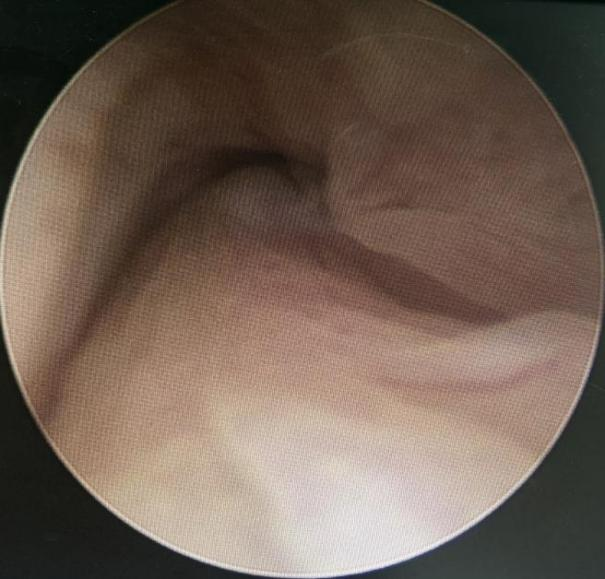

为明确宫颈肌瘤的分型,建议其先行宫腔镜检查术。患者表示诧异,觉得自己未婚且无性生活史,可以做宫腔镜检查术吗?医务人员耐心解释,使用內鞘直径2.7mm的宫腔检查镜,通过宫腔镜的阴道内镜技术,不需要阴道窥器,纤细的检查镜可以顺利通过处女膜孔而不破坏处女膜,也无需扩张子宫颈即可完成宫腔镜检查术。

患者同意治疗方案,术中检查提示宫颈黏膜下肌瘤(0型),建议其住院手术治疗。